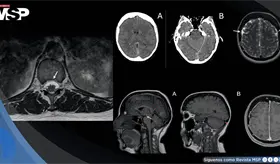

El procedimiento es esencial para diagnósticos complejos, ya que permite analizar directamente el tejido del corazón, siendo clave no solo en el monitoreo de trasplantes, sino también en enfermedades infecciosas y cardiopatías infiltrativas.